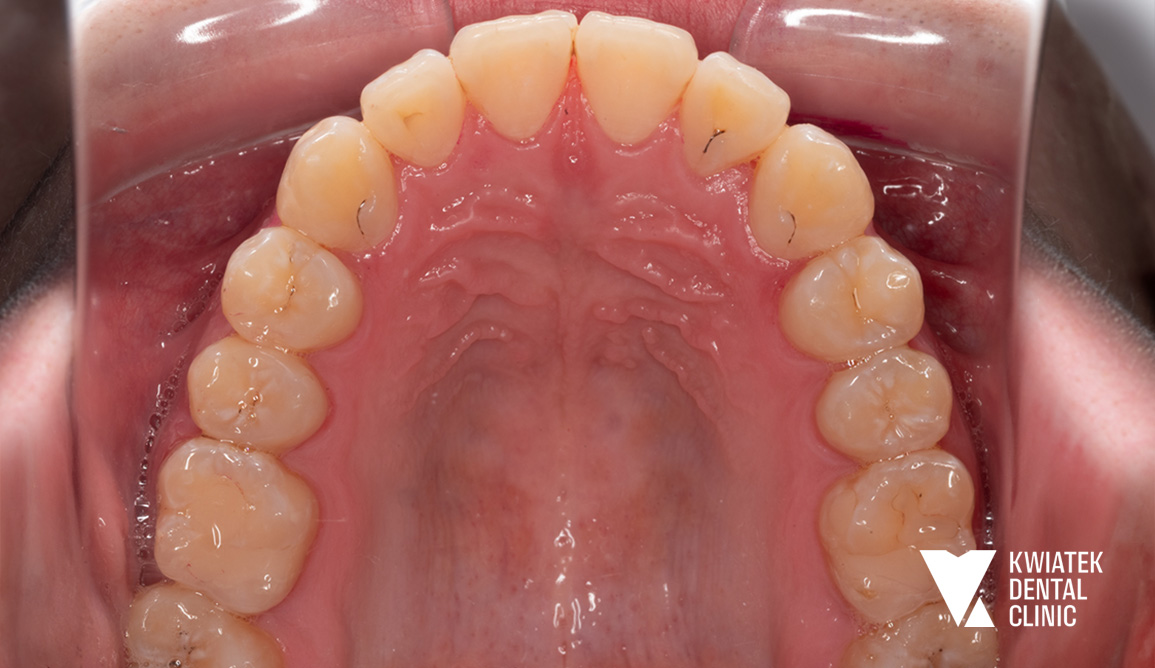

PRZED

PO

• zgryz krzyżowy zęba 12

• znaczny deficyt miejsca dla zębów 12 i 13

• wychylenie przedsionkowe zęba 13

Uzyskano prawidłowe ustawienie zębów w łukach, korektę zgryzu krzyżowego, właściwą relację zgryzową oraz harmonijną estetykę uśmiechu. Metamorfoza pokazuje, jak dzięki dokładnej diagnostyce, nowoczesnym technikom ortodontycznym oraz konsekwentnemu prowadzeniu leczenia można osiągnąć stabilny i naturalny efekt bez konieczności usuwania zębów przedtrzonowych.